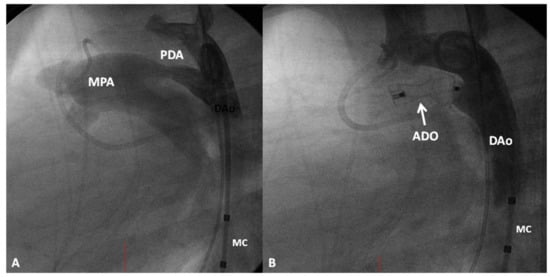

8.3. Type of Intervention